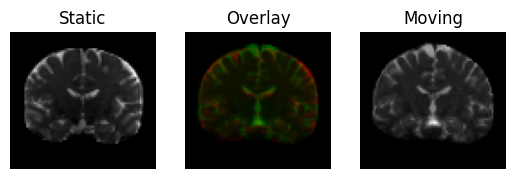

plot the overlapped middle slices of the volumes

regtools.overlay_slices(

static,

resampled,

slice_index=None,

slice_type=1,

ltitle="Static",

rtitle="Moving",

fname="input_3d.png",

)

<Figure size 640x480 with 3 Axes>

Static image in red on top of the pre-aligned moving image (in green).